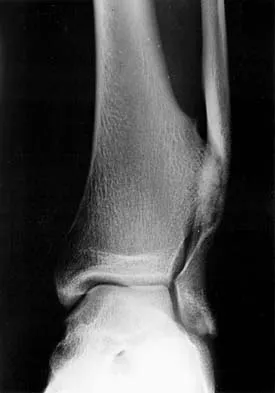

Question 70

Figures 3a and 3b show the inversion stress radiographs of a patient's ankle. What is the most likely ligament injury pattern?